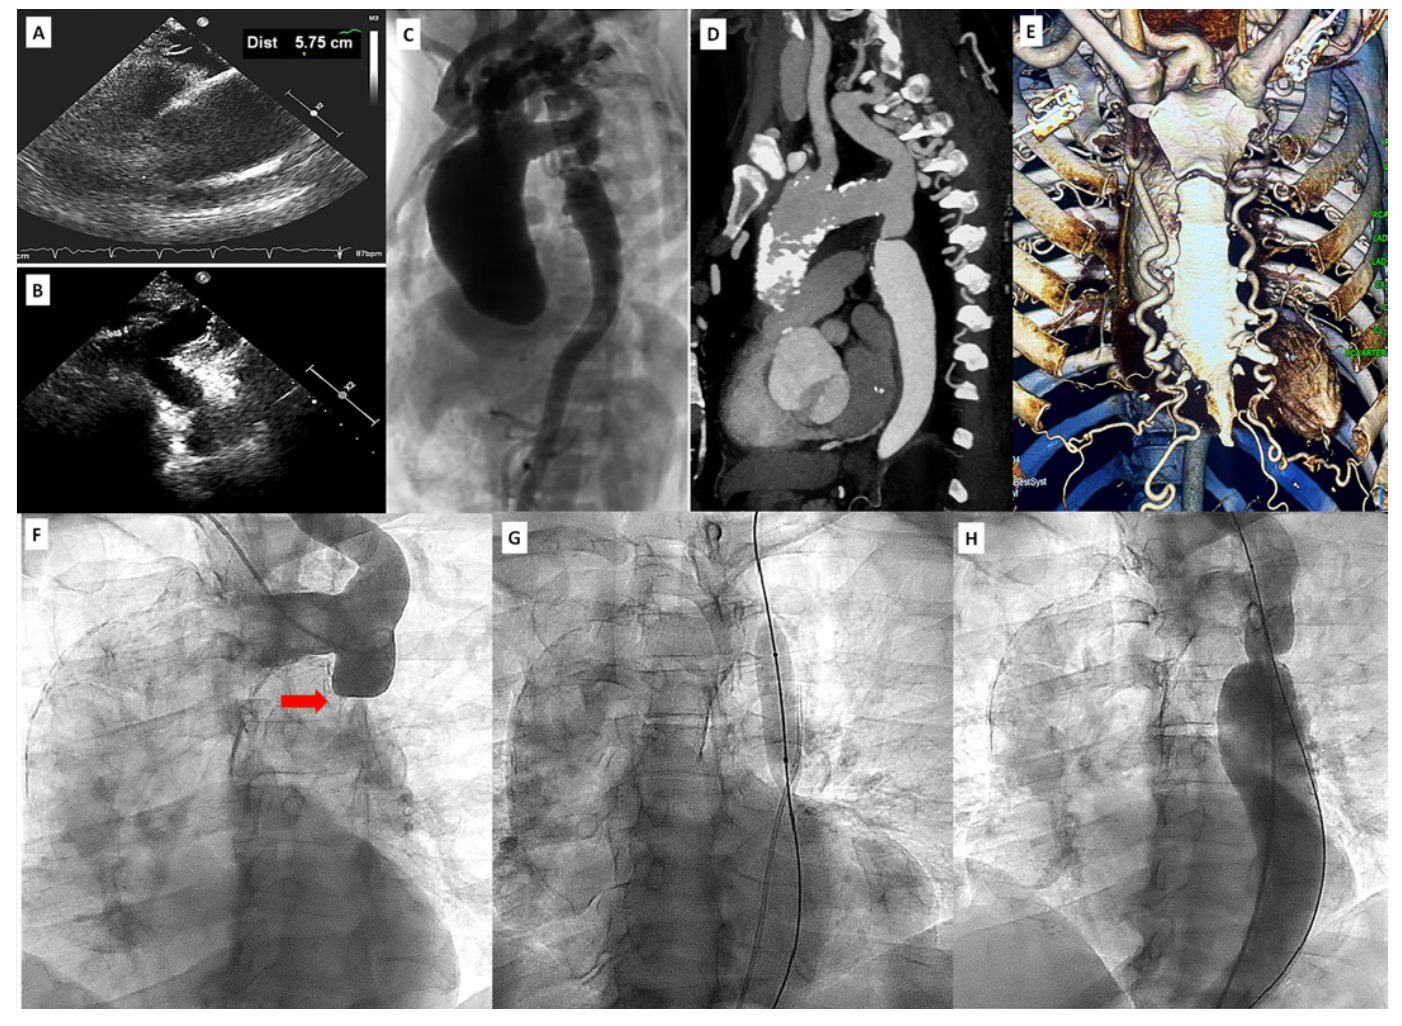

A 52-year-old diabetic, hypertensive male presented with progressive dyspnea and palpitation for the last 3 months. Clinical examination revealed low blood pressure in lower limbs with an ankle-brachial index (ABI) of 0.50. Systemic examination revealed bilateral basal crepitations and left ventricle (LV) third-heart sound. An electrocardiogram showed atrial fibrillation with ventricular rate of 120 bpm. Two-dimensional echocardiography revealed LV ejection fraction of 30%, global LV hypokinesia, no mitral regurgitation, and normal tricuspid aortic valve. The ascending aorta was dilated, having a maximum dimension of 5.75 cm (Figure 1A). The suprasternal view showed a coarcted segment of the descending thoracic aorta (DTA) distal to the origin of the left subclavian artery (Figure 1B). A computed tomography angiography revealed aneurysmal dilation of calcified ascending aorta (Figure 1C) having a maximum dimension of 69.5 mm (Figure 1D). The DTA showed >95% focal narrowing suggestive of coarctation of aorta (CoA) (Figure 1D). There were extensive arterial collaterals from both internal thoracic arteries (Figure 1E).

Following the medical treatment for LV failure and fast ventricular rate, catheterization was performed. Coronary angiography was normal. The ascending aorta was dilated and calcified. An aortic arch angiogram showed CoA (Figure 1F) having a gradient of 80 mm Hg. A 0.035-inch, straight, hydrophilic-tip guidewire could cross across the coarcted segment through left radial access. It was sequentially dilated with 6 x 40-mm followed by 12 x 40-mm peripheral angioplasty balloons (Cook Medical) (Figure 1G). Post angioplasty, there was no residual gradient and a brisk flow was achieved across the DTA (Figure 1H; Video Series). He had symptomatic improvement at 6-month follow-up exam. The open surgical aortic arch repair was not performed, as the patient was not willing to undergo further intervention.